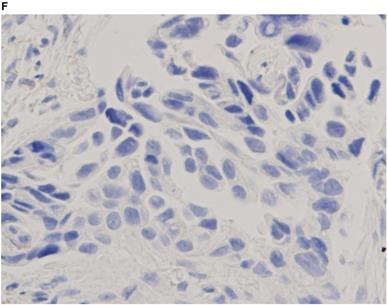

Representative images of PD-L1 immunohistochemistry staining of tumor cells obtained via EBUS-TBNA and TBB are shown in Figure 2.

Figure 2

Immunohistochemistry characterization. Representative images of programmed death ligand-1 immunohistochemistry staining of tumor cells obtained via endobronchial ultrasound-guided transbronchial needle aspiration (A tumor proportion score [TPS] ≥50%, B TPS = 1‒49%, C TPS <1%) and transbronchial biopsy (D TPS ≥50%, E TPS = 1‒49%, F TPS <1%) (40x magnification).